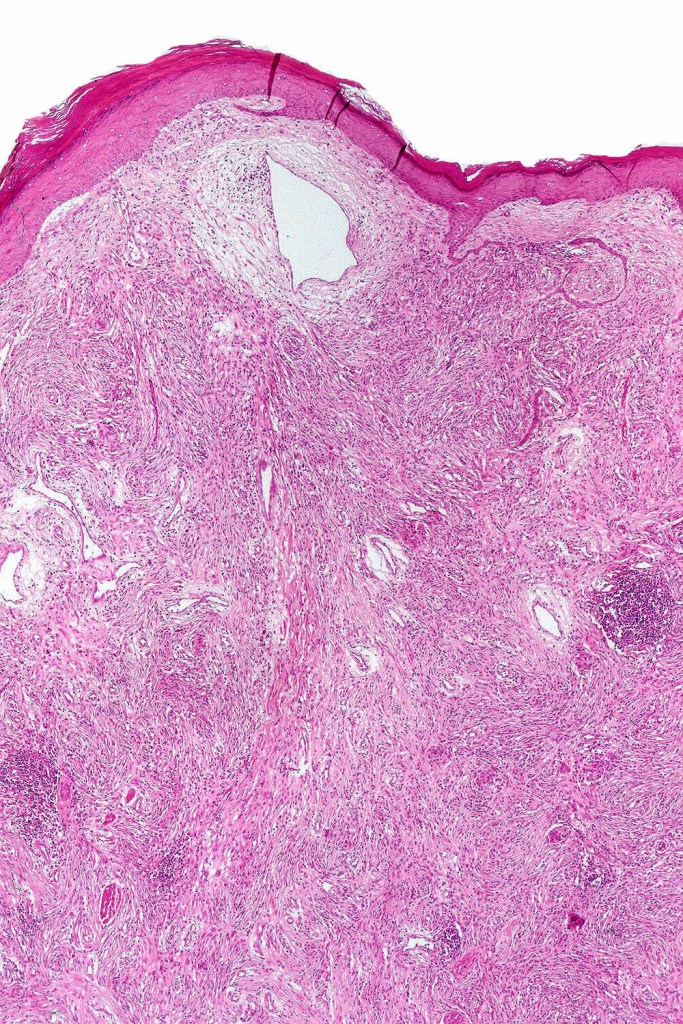

Common blue nevus

Common blue nevus shows a predilection for the backs of the hands & feet, buttocks, face & scalp althought any site can be affected. It presents as a sharply delineated approximately 1.0 cm diameter slate blue or blue/black papulo/nodule. Congenital, eruptive, targetoid, plaque & desmoplatic/hypopigmented variants are recognised. Common blue nevi have also been described in the cervix, oral mucosa, conjunctiva & sclera, breast etc.

Exceptionally, melanoma is a complication

Histologically, it is characterized by a dense population of spindled, dendritic melnanocytes & melanophages with variable fibrosis. It may sometimes represent a component of a combined nevus. Mitotic activity is not usually present and pleomorphism is absent (see atypical blue nevus below). Involvement of the arrector pili muscle is not uncommon.

Very exceptionally, blue nevus also involves the epidermis (compound blue nevus).

Cellular blue nevus

This uncommon most often devlops on the buttocks, sacrococcygeal region & distal extremities although it may be seen at just about any site. It shows a predilection for females and is diagnosed most often in the 2nd-4th decade. It presents as a blue-black/ or black nodule measuring 1-2 cm in dianeter. Similar to common blue nevus, the cellular variant can be encountered in a wide range of non-cutaneous locations.

Histological features

•Most characteristic is the dumbbell silhouette although a plague morphology may also be encountered

•Combined nevus variant

•Admixture of spindle cells, pigmented bipolar or dendritic cells & melanophages

•Cytoplasm is pale and nuclei are small with inconspicuous nucleoli

•An alveolar pattern is characteristic particularly with clear cell nodules

•Mitoses are typically very sparse or absent

•No atypical mitoses

•No Necrosis or lymphovascular invasion

•Multinucleate giant cells sometimes present

•Stromal fibrosis, myxoid change, vascular hyalinization with cyst formation are often seen

•Some tumors are composed spindle cells in a fascicular or neuronevoid pattern

•Perineural involvement may be seen

•Balloon cell change

•Desmoplastic variant

•Hypopigmented variant